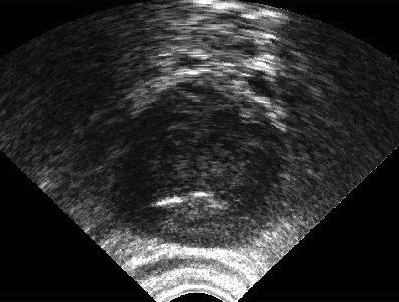

It is a challenge to validate any approach to segmentation. One has to measure the accuracy of the segment against ground-truth images. Ideally, if we have many users available to segment images, we can build “consensus segments”, or gold standard, to make more reliable measurements. Of course, this is usually not feasible with real images, for which there is no gold standard. Hence, we generated synthetic images whose gold segments were known a priori. For this reason, we used synthetic images that simulate transrectal ultrasound (TRUS).

TRUS images of prostates may be used to both diagnose and treat prostate diseases such as cancer. Starting with a set of prostate shapes , we created random segments through combinations of those priors, adding noise along with random translations and rotations, and we distorted the results with speckle noise and shadow patterns. Each image is thus created from its gold . Consequently, we can simulate user delineations by manipulating via scaling, rotation, and morphological changes, and we can simulate edits by running active contours with variable user-simulating parameters. The variability of user delineations was simulated according to several factors: error probability (), anatomical difficulty ( out of ), and the scaling factor for morphology (form to ). The user was modelled according to the level of experience (a random number from ), the user’s attention (a random number from ), and the user’s tendencies in terms of the segment size (a random number from ), whether tending to draw contours that are relatively small () or large ().

We generated 500 images from their corresponding gold-standard images111All images and their segments are available online: http://tizhoosh.uwaterloo.ca/. Furthermore, we generated 20 different segments for each image, assuming that there were 20 users. Figure 4 shows five examples of real and synthetic TRUS images. One should bear in mind that the purpose here was not to simulate the images realistically, but rather to have a base from which to generate variable segments from a perfect segment. Figure 5 shows an example of the gold segments and simulated user contours. The variability, coupled with the gold segment, is what is needed in our experiments.